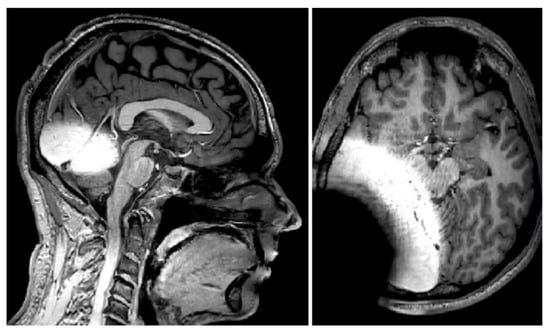

- Majdani, E.; Majdani, O.; Steffens, M.; Warnecke, A.; Lesinski-Schiedat, A.; Lenarz, T.; Götz, F. Dimensions of artefacts caused by cochlear and auditory brainstem implants in magnetic resonance imaging. Cochlear Implants Int. 2020, 21, 67–74. [Google Scholar] [CrossRef] [PubMed]

- Majdani, O.; Rau, T.S.; Götz, F.; Zimmerling, M.; Lenarz, M.; Lenarz, T.; Labadie, R.; Leinung, M. Artifacts caused by cochlear implants with non-removable magnets in 3T MRI: Phantom and cadaveric studies. Eur. Arch. Otorhinolaryngol. 2009, 266, 1885–1890. [Google Scholar] [CrossRef] [PubMed]